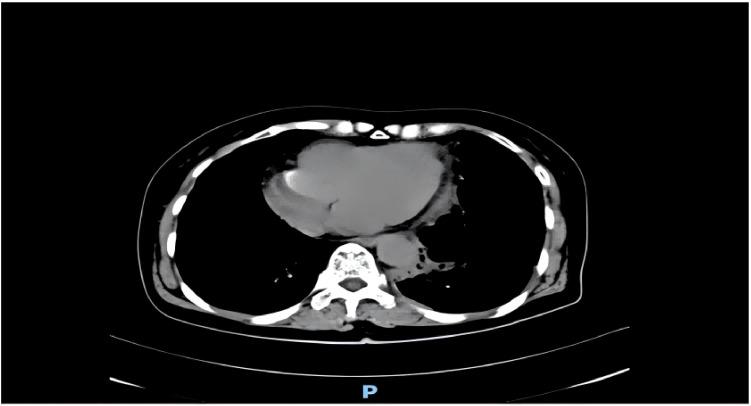

This case report describes the successful resuscitation of a 54-year-old female who experienced cardiac arrest following resection of a giant mediastinal tumor (GMT). The patient's hemodynamic collapse was attributed to mediastinal mass syndrome, mediastinal swing, and acute re-expansion pulmonary edema. This report highlights the challenges of perioperative management in GMTs, emphasizing the importance of multidisciplinary preoperative planning, continuous hemodynamic monitoring, and prompt intervention during complications. Early recognition of hemodynamic instability, coupled with adherence to advanced resuscitation protocols, is critical for improving survival in high-risk mediastinal tumor surgeries.

本病例报告描述了一名54岁女性在巨大纵隔肿瘤(GMT)切除术后发生心脏骤停并成功复苏的过程。患者的血流动力学崩溃归因于纵隔肿块综合征、纵隔摆动和急性复张性肺水肿。本报告强调了GMT围手术期管理的挑战,强调了多学科术前规划、持续血流动力学监测以及并发症发生时及时干预的重要性。早期识别血流动力学不稳定,并坚持采用高级复苏方案,对于提高高风险纵隔肿瘤手术的生存率至关重要。